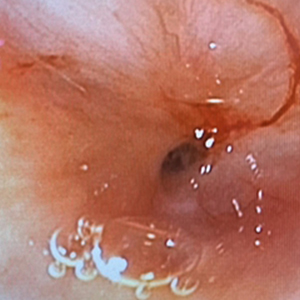

気管の内視鏡検査

スワブ生検

気管虚脱に加え、スワブ検査で炎症が見られました。